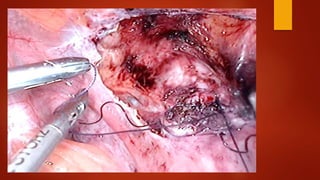

Суть метода После вскрытияпузырно-маточной складки брюшины и низведения мочевого пузыря при помощи монополярного электрода типа «Игла» рассекается рубец.

Края рубца «освежевываются»с помощью ножниц без использования энергий. Далее стенки матки ушиваются синтетической рассасывающейся нитью «Викрил» №1 отдельными швами в два ряда. Перитонизация.